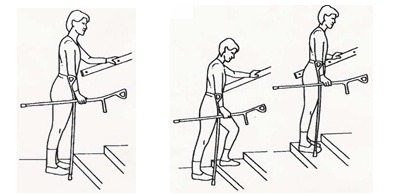

نکاتی در مورد بالا و پایین رفتن از پلهها: پلکان با نرده

هنگام بالا رفتن از پلهها با یک دست از نردهها بگیرید و چوبهای زیر بغل را در دست دیگر بگیرید. ابتدا پای سالم را روی پله بالایی بگذارید، سپس پای عمل شده را بالا ببرید و در نهایت چوب زیر بغل را روی پله بالایی بگذارید.

هنگام بالا رفتن از پلهها با یک دست از نردهها بگیرید و چوبهای زیر بغل را در دست دیگر بگیرید. ابتدا پای سالم را روی پله بالایی بگذارید، سپس پای عمل شده را بالا ببرید و در نهایت چوب زیر بغل را روی پله بالایی بگذارید.